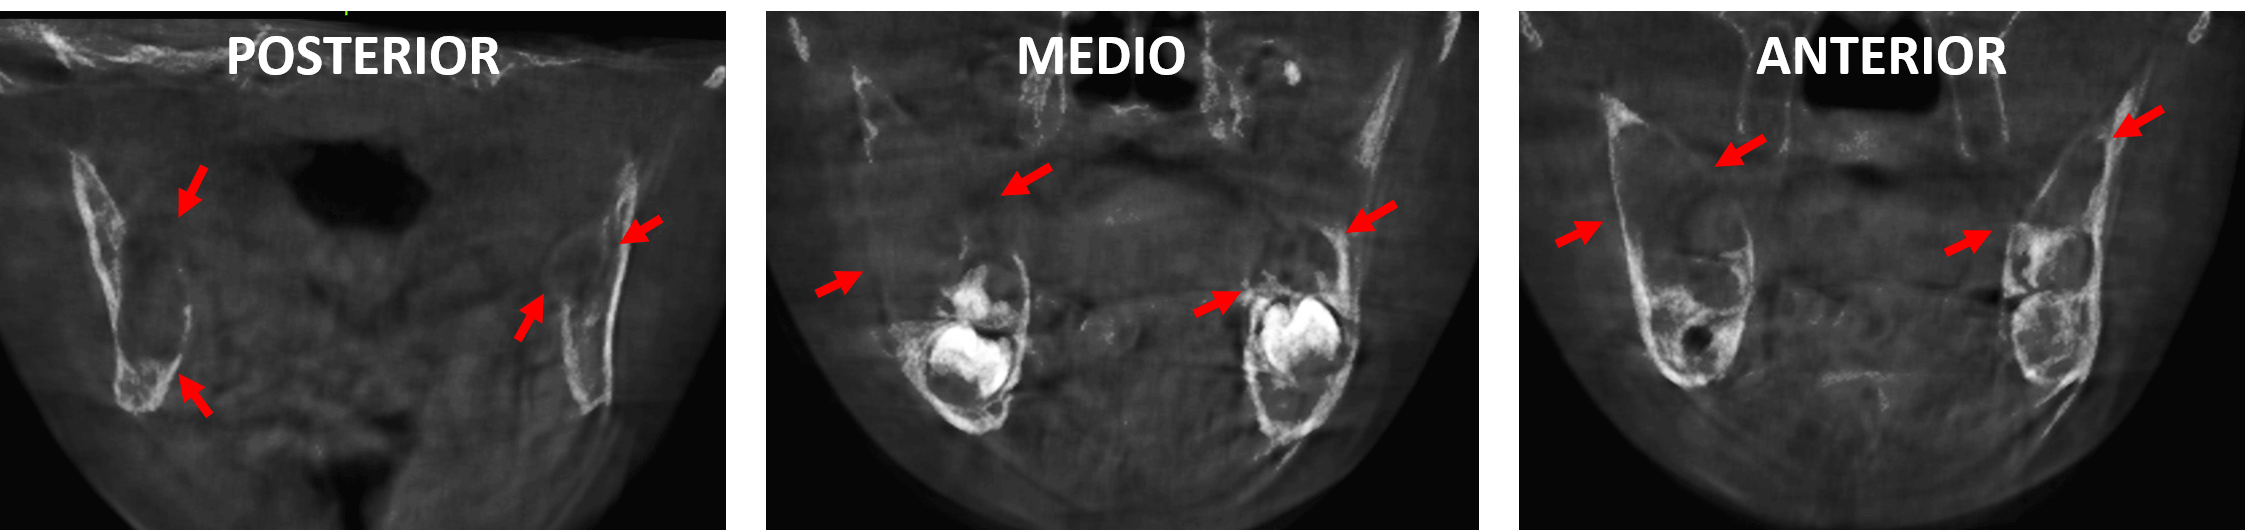

Fig.5

En cortes axiales (Fig.5) se observa también el compromiso de las tablas óseas en ambas ramas ascendentes, condicionando la leve expansión, adelgazamiento y probable erosión de las corticales óseas.